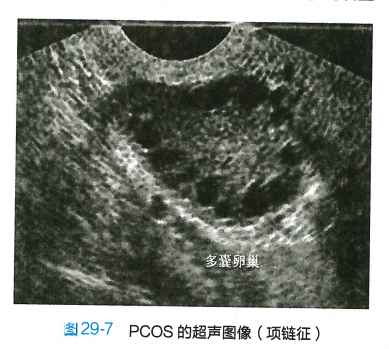

2.超声检查 见卵巢增大,包膜回声增强,轮廓较光滑,间质回声增强;一侧或两侧卵巢各有12个及以上直径为2~9mm无回声区,围绕卵巢边缘,呈车轮状排列,称为“项链征”(图29-7)。连续监测未见主导卵泡发育及排卵迹象。